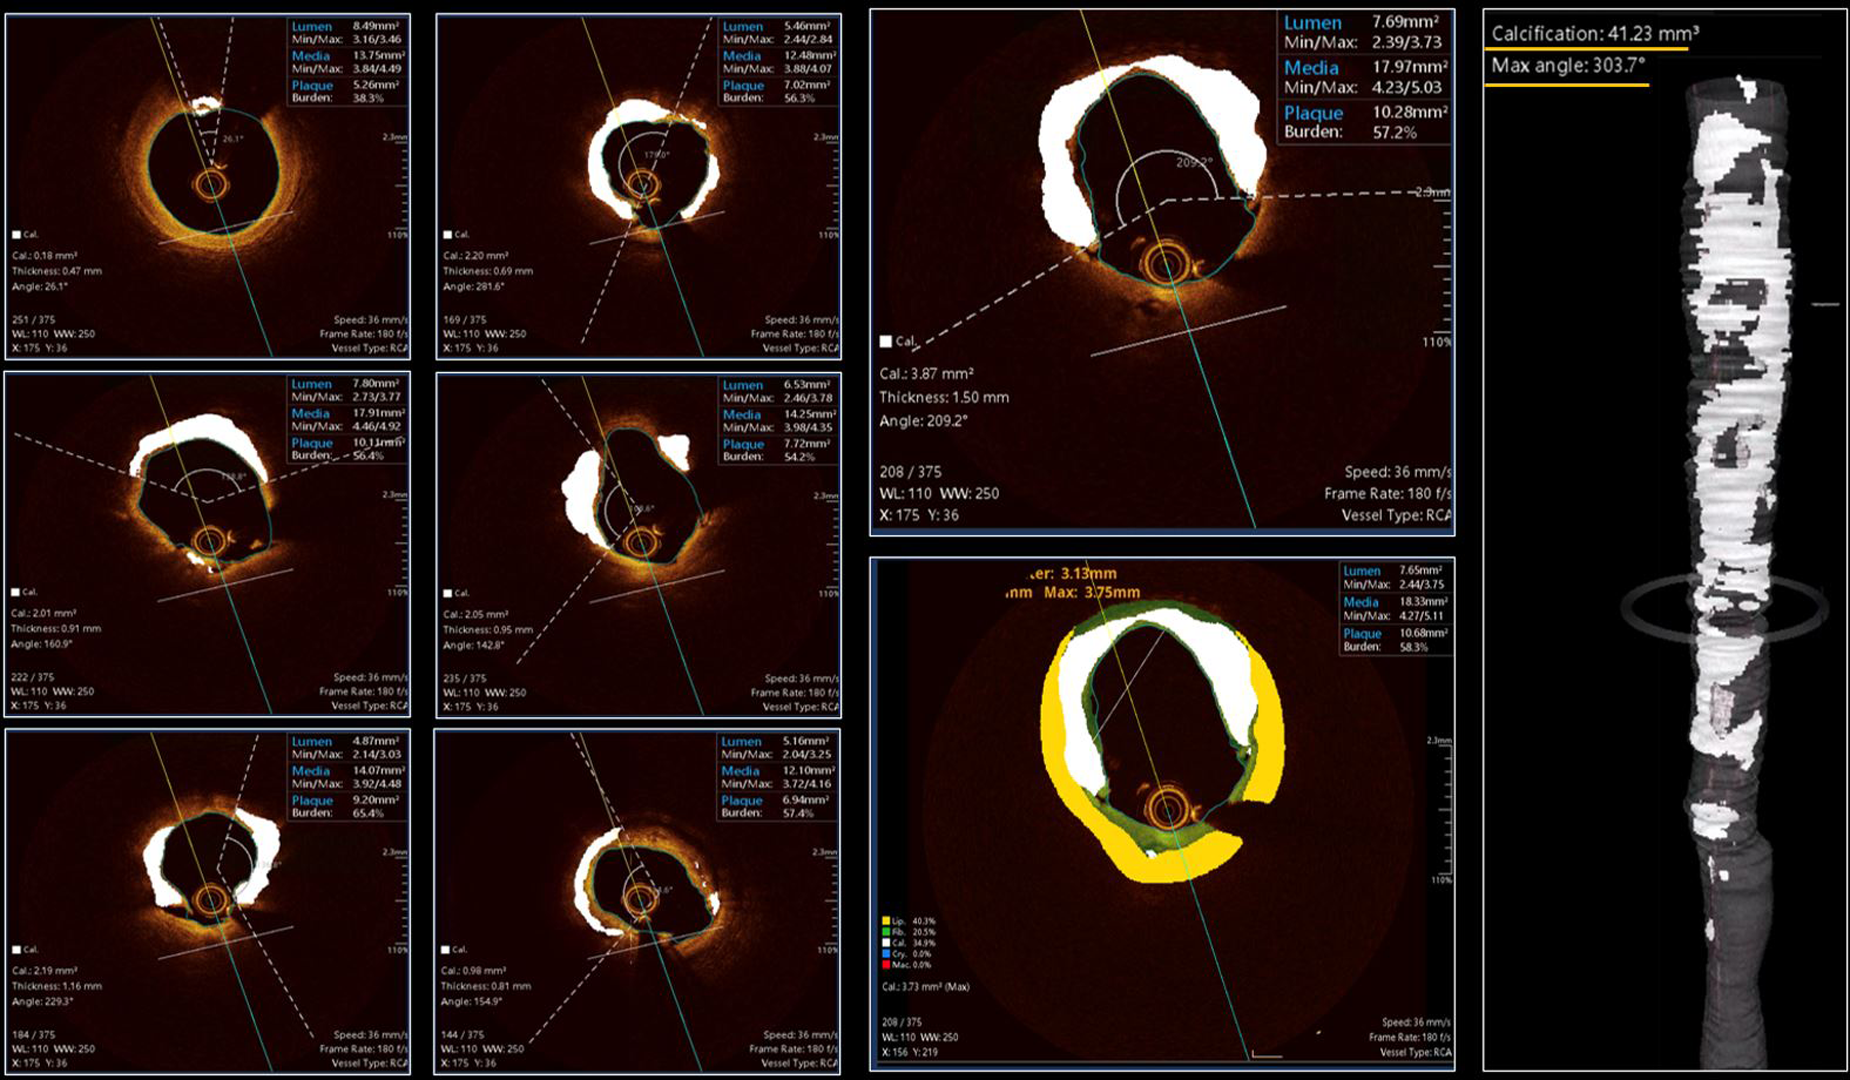

One of the most recent advancements in OCT technology is the availability of artificial intelligence (AI)-based software (Ultreon 1.0 Software, Abbott, US; OCT-Plus, Pulse Medical, China), which is able to automatically select and characterize CAC in a real-time and fully automated fashion with the additional benefit of removing an operator's interpretation bias. In a proof-of-concept study including 10,517 training set images and 1,156 testing set images, an AI-based approach was able to detect CAC with an accuracy of 88.5% (33). An example of the OCT-Plus software interface is provided in Figure 6 and that of Ultreon is provided in Figure 7.

Figure 6

Case example applying OCT-plus package for automated detection of calcium burden and distribution. The six panels on the left provide insights about all features of OCT-patterns of calcium. The large two panels in the middle, provide high detailed image of calcium distribution and its possible combination with non-calcified tissues [lipidic (yellow) or fibrotic (green)]. The reconstruction on the right provide clear overview of longitudinal distribution of calcium and provide details about the maximum angle of calcium and total calcium volume in mm3.